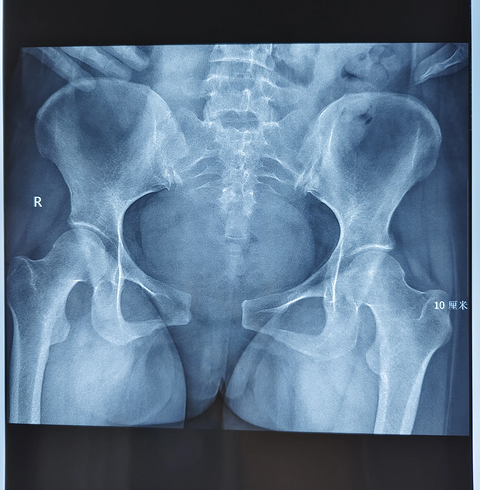

产后三天发现耻骨联合分离达4.8厘米,无法下地行走

看到一位医生分享的,一位准妈妈,产后三天发现耻骨联合分离达4.8厘米,无法下地行走,卧床休息时腿都得屈着,太痛苦!后经会诊给予正骨复位治疗四天后,耻骨联合分离恢复到1.7厘米,很有成就感啊!

顺产后12天,耻骨联合分离导致疼痛,一检查发现分离了4.5CM

知道生孩子会导致耻骨分离,但是这个妈妈分离4.5厘米有点吓人哦,4.5厘米大概有————————差不多这么宽吧?据说勒个妈妈孩子出生体重4050克,产后当天就不能翻身、下床。产后一周才能在家属搀扶下站立,但却无法正常行走,只能侧身挪步前行。 所以说孕期体重控制还是很重要,娃儿太大了,最后受罪的还是大人。